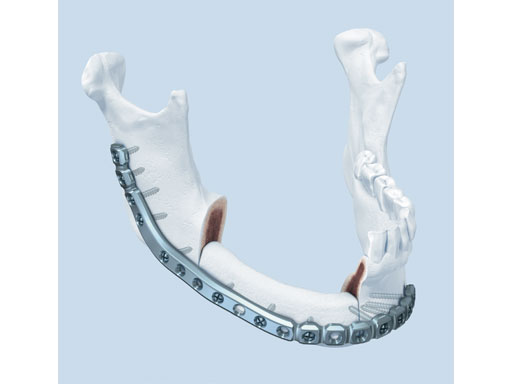

Matrix Mandible SystemPreformed Reconstruction Plate

One of the biggest challenges in mandibular reconstructive procedures is the bending of the large (or heavy) reconstruction plates. Not only can this become a time-consuming process, the bending tools can also introduce stress into the plate and even leave marks. Oftentimes this can lead to reduced fatigue life of the implant. The new preformed reconstruction plate was designed based on the matrix mandible systems 2.5 mm (light blue) plates to overcome the effects of plate fatigue due to overinstrumentation.

The preformed plates provide a 3-D shape which is based on the statistical analysis of mandible models obtained from over 2,000 CT scans, originating from various adult populations in collaboration with Marc C Metzger (Freiburg, Germany) who had already played a crucial part in developing the preformed orbital plate from the matrix orbit system.

Fig 1 Preformed reconstruction plate.

The plates are available in three sizes: small, medium, and large with each plate offering a section of increased strength in the body and angle regions. The anatomical shape of the preformed reconstruction plates also allows for transoral application, ie, in combination with transbuccal instrumentation and/or the 90 screwdriver. The minimal intraoperative bending that is required preserves the optimal threaded-hole shape, especially in the preformed sections. These features result in a plate with increased fatigue life compared to standard reconstruction plates, thus reducing the risk of plate failure.

The preformed mandible reconstruction plates are intended for use in oral and maxillofacial surgery, trauma, and reconstructive surgery. This includes primary mandibular reconstruction, comminuted fractures, and temporary bridging until delayed secondary reconstruction, including fractures in edentulous and atrophic mandibles, and unstable fractures. They are 2.5 mm thick and are made from pure titanium. They can be used with the light blue locking screws (2.4 mm) from the matrix mandible system. Anatomically preformed sizers facilitate the correct plate size selection in the OR.